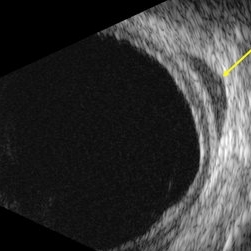

B-scan echography uveal lymphoma with orbital involvement

Jan 20 2023 by Elaine Michele Binkley, MD

B-scan echography (T10) shows a hypo-echoic mass posterior to the globe consistent with orbital involvement of uveal lymphoma.

Photographer: Laura Warner, University of Iowa

Condition/keywords: Uveal lymphoma